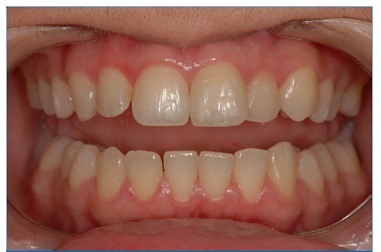

Clinical and radiographic follow‑ups were performed after 6 months, and then 3, 7, 8, 9, and 10 years. In the 10‑year control, the patient remained asymptomatic. Her teeth 11, 12, and 23 continued to respond positively to the sensitivity tests and seemed to be in function (Figure 5). Root fracture’s consolidation with rounding of the fracture edges, calcification of the apical third, bone formation between the fragments, and absence of periapical lesion or root resorption were noted radiographically (Figure 6). Moreover, the obturation paste of calcium hydroxide associated with 2% chlorhexidine gel and zinc oxide was still filling the root canal of teeth 21 after ten years.